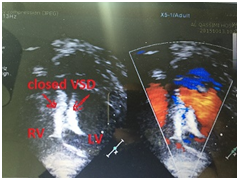

Patient was observed gain in cardiac intensive care unit and his vital signs started to be more stable so that IABP was removed and gradual weaning from high doses inotrops was achieved within 4 days. After 7 days patient was extubated and kept under observation due to pneumonia and CNS disturbances but after 10 days he improved dramatically and shifted to the ward before discharge home. Final echocardiography showed: VSD device in place with trivial residual shunt (Figure 4).